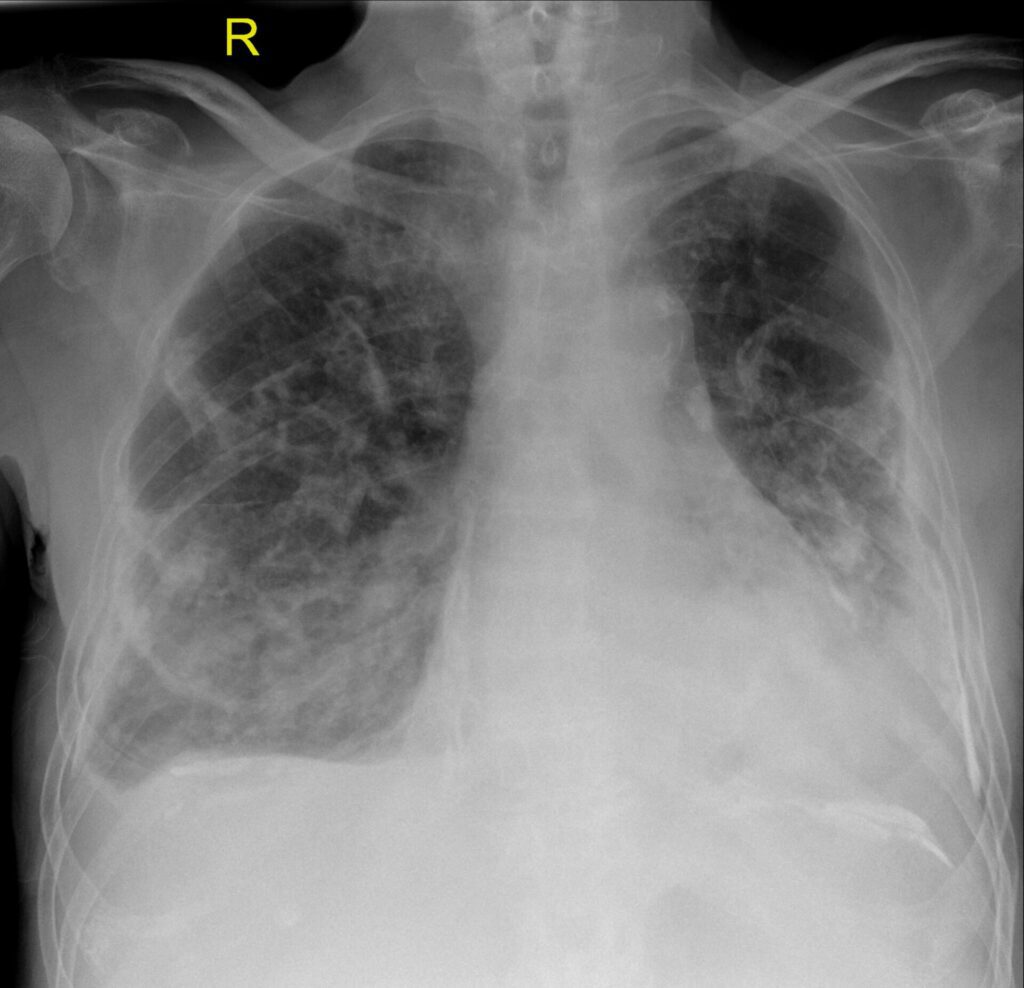

Röntgen-Thorax

Der Röntgen-Thorax ist häufig die erste Untersuchung. Typische Zeichen einer Pleuritis calcarea sind:

- lineare oder flächige, scharf begrenzte Pleuraverkalkungen entlang der Thoraxwand,

- verkalkte pleurale Plaques im diaphragmalen Bereich, meist lanzettenförmig,

- links oder rechts betonte, teils bilaterale Befallsmuster,

- Volumenminderung mit Zwerchfellhochstand und Verziehung der Thoraxkontur (Fibrothorax),

- ggf. basale streifige Verdichtungen, die sekundäre Atelektasen widerspiegeln.

Ein wichtiges radiologisches Problem ist die Abgrenzung von chronisch organisierter Pleura gegenüber einem noch bestehenden, teils verkapselten Erguss. Hier stösst das p.a.-Röntgen an seine Grenzen.